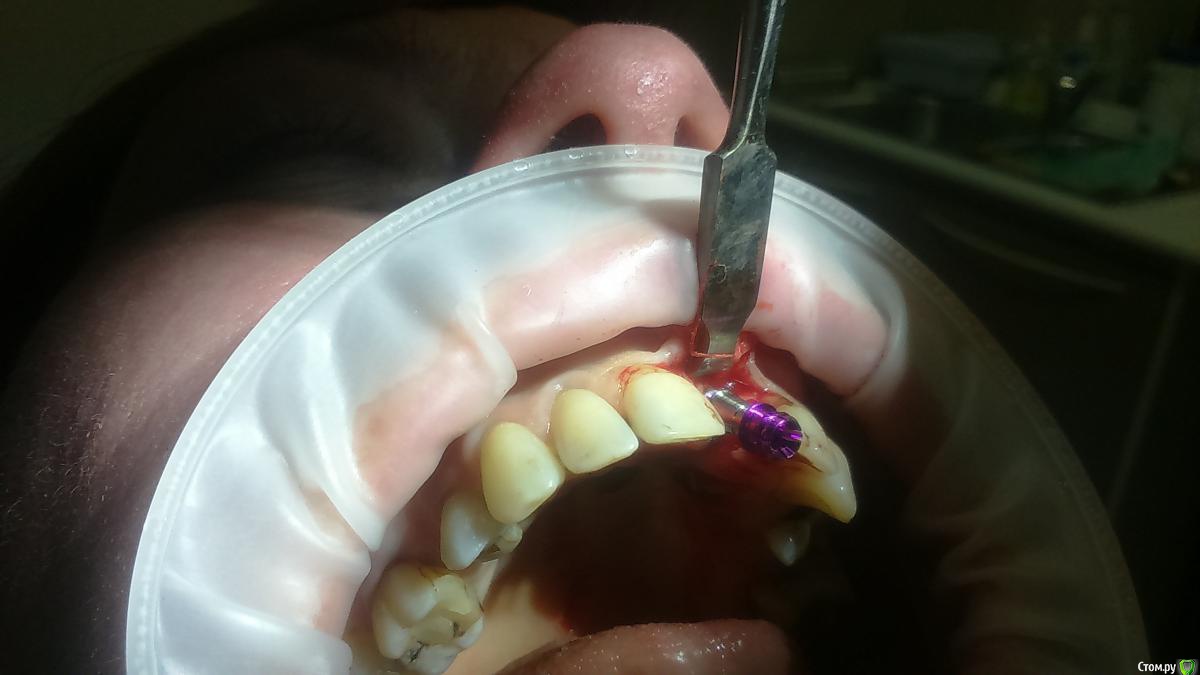

Platon Опубликовано 31 января, 2016 Автор Поделиться Опубликовано 31 января, 2016 Продолжение.не судите строго за фото, первый раз вообще фоткаю операцию)спасибо за советы.По порядку. После того, что мне написали, я решил все -таки уговорить на конусный имплантат (3.7-11.5 ImplantDirect). Также ортопед не хотел делать временную коронку, сказал что сделает каппу, птичку в топку -тоже сделали. Слизистая в области 21 была в рубцах. Исходя из этого всего я решил, коль временной коронки не будет, то сст подсаживать тоже не стану пока,(ортопеда уговаривал сделать временную коронку)))- торк был хороший 35-50н) для того чтобы сст попрактиковаться, но(((.в итоге, анестезия, разрез, сверло пилотное и сверло 2.2, далее расщепление с помощью набора майзенгер с использованием спредеров до нужного диаметра, установил имплантат, торк контролируемый, можно было подобрать любой) в итоге оставил 35. заглушка, совсем немного ксено, мембрана, ушился. ждем. Будет что-то типо каппы которая слегка отдавливает десну,формируя сосочки. не знаю, ни разу такую еще не видел.планирую на этапе раскрытия все-таки сст и временную коронку увидеть.вот. через 4 мес. выложу, что получилось) Если есть советы, критика, всему буду рад, спасибо 3 Ссылка на комментарий

Заурбек Опубликовано 1 февраля, 2016 Поделиться Опубликовано 1 февраля, 2016 Доброго времени суток. После работы спредерами сразу установили имплантат или прошлись финишной фрезой? Мембрану ничем не фиксировали? Покажите фото каппы?) Ссылка на комментарий

Platon Опубликовано 3 февраля, 2016 Автор Поделиться Опубликовано 3 февраля, 2016 Доброго времени суток. После работы спредерами сразу установили имплантат или прошлись финишной фрезой? Мембрану ничем не фиксировали? Покажите фото каппы?)после работы спредерами ничего больше не сверлил, но спрелерами долго работал, не спеша, по одному два витка и ждал некоторое время, и так поменял 3-4 спредера пока до нужного размера не дошел.каппу постараюсь в четверг сфоткать Ссылка на комментарий